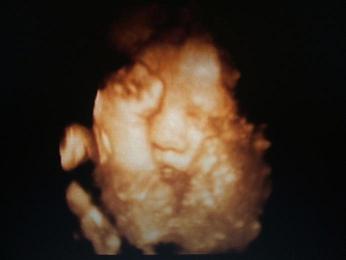

Majd végre következett a 4D, amit már nagyon régen vártunk!!! Mátéval megbeszéltük, hogy mindent szépen megmutatt, persze nem így történt.

Az arcocskáját alig láttuk, mert a Placentát teljesen maga elé húzta, majd az idő elteltével nem volt neki elég a placenta, a kis kezével s takargatni kezdte megát.....Hát nagyon szomorúan mentünk haza és csalódottan. Az egész délutánunkat megpecséltete, csak az vigasztalt, hogy nem sokára élőben láthatjuk majd.....és akkor nincs menekvés neki........

Azért dobok egy képet: Kép

Azért én látok ott egy helyes nózit, egy szájacskát.. :)

Kis pupu: annyira gyönyörű a babád! Számomra még mindig felfoghatatlan, hogy ide jutott a technika... szinte élőben láthatjuk ki lakik odabenn... ez csoda! :)